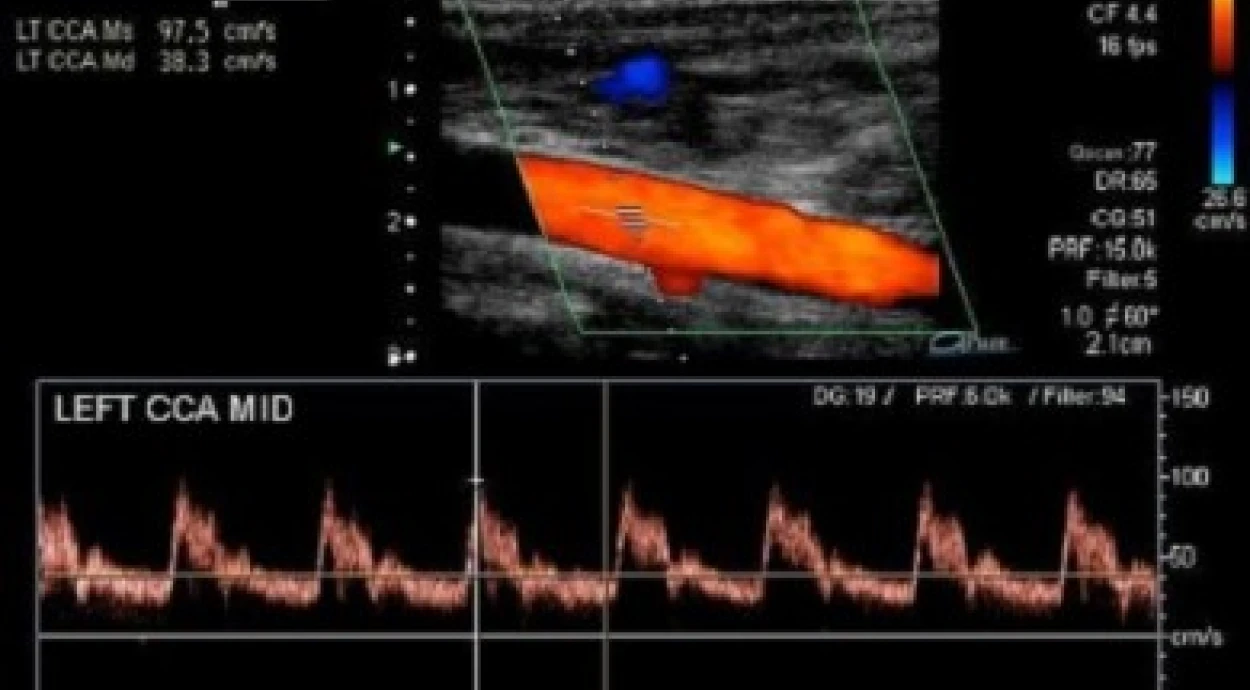

Доплер-діагностика судин є одним з методів дослідження кровотоку в різних частинах організму. З її допомогою можна визначити швидкість та напрямок течії крові у венах та артеріях, тиск всередині судин та ширину просвітів в них.

Доплер – це спеціальний датчик для ультразвукових досліджень. Його робота заснована на однойменному ефекті, який полягає в зміні частоти звукових хвиль при відображенні від рухомих об'єктів. Збільшення частоти каже, що об'єкт рухається в сторону датчика, зменшення – від нього. Сам зсув частот пропорційний швидкості об'єкта.

При доплерографії голови та шиї перевіряють сонні, підключичні та хребетні артерії, магістральні артерії головного мозку та вени шиї. Показаннями до проведення цього дослідження можуть бути скарги на головні болі та раптову втрату свідомості, шум у голові та вухах, інсульт, надмірна вага, підвищений рівень холестерину, вегето-судинна дистонія, стенокардія, інфаркт та інші хронічні хвороби.